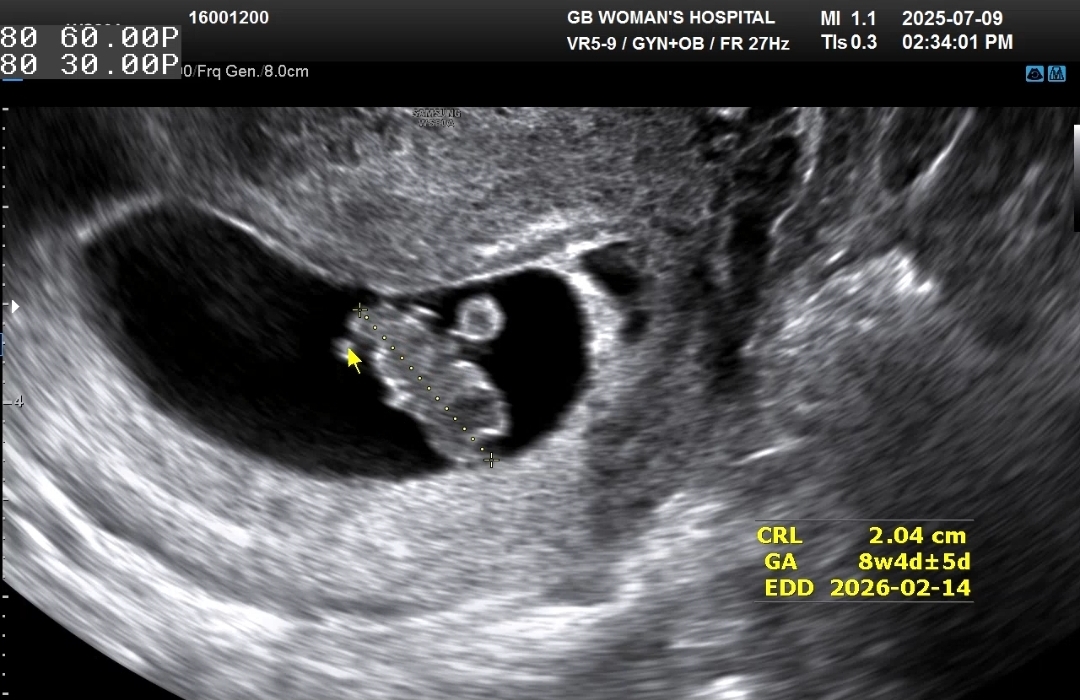

입덧약 받는 김에 본 초음파에서 아기크기는 1.64cm로 실제 8주0일 크기였다 ㅋㅋ 쑥쑥 잘 크고 있군!!

심장소리도 167bpm으로 주수에 맞게 아주 잘 뛰고 있었다!!